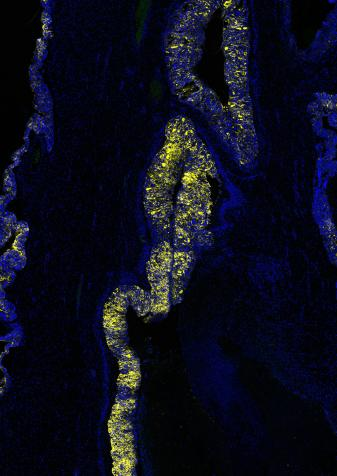

图二:使用 NaveniFlex™ Atto647N 检测透明细胞癌恶性卵巢组织中间皮素与粘蛋白的相互作用,精准定位肿瘤微环境中的分子关联。